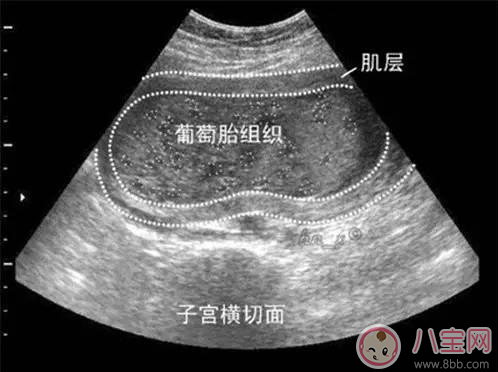

葡萄胎是由于絨毛膜滋養(yǎng)層細(xì)胞異常增生,絨毛發(fā)生水腫變形,呈無數(shù)個(gè)水泡相互連接,形似成串的葡萄,故名曰葡萄胎,又被稱為“水泡樣胎塊”?;加衅咸烟ヒ坏┐_診后要刮宮處理。如果子宮不大,內(nèi)容物比較少,那么一次就可以刮干凈,對(duì)女性子宮的傷害也較小,但是如果內(nèi)容物比較多,有數(shù)不清的水泡,會(huì)轉(zhuǎn)移,一次很難刮干凈,那么需要兩次刮宮。